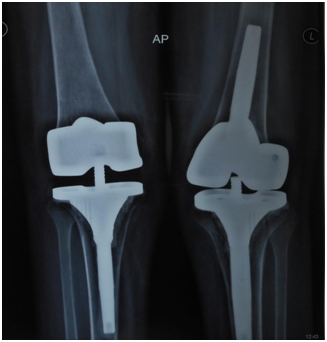

After 2weeks, her condition was reassessed and it was decided to operate both the knees in the same sitting. Patient was given general anesthesia and left knee was operated first, under tourniquet. Medial parapatellar approach was used (Figure 8), patella was found fused to the underlying femur condyles and was mobilized using sharp osteotomes taking care not to damage the condyles. Synovectomy was done, lateral and medial gutters were cleared and quadriceps was mobilized too, but patella could not be everted. Knee joint line was identified by the horizontal depression between femur and tibia and was carefully osteotomized using saw removing a wedge of bone (Figure 9). Further soft tissue release was done from posterior aspect of tibia and femur so that the tibia could be subluxated enough to take 8mm proximal tibial cut perpendicular to its mechanical axis and keeping the posterior slope to minimum. To create some extension space, 4mm thicker distal femur cut was taken and posterior capsule was lifted off the femur. After taking other cuts in proper orientation, trial was done which revealed varus-valgus instability and around 60degrees of persistent flexion deformity. So additional distal femur cut had to be taken and a constrained knee implant (Total stabilizing, Stryker) was used. Figure 6 & 7 After final implantation, there was no instability but 30degrees of flexion deformity persisted. Similarly, right knee was operated but instead of a constrained system, use of just a constrained liner and tibial stem gave satisfactory stability. Both the knees were closed in layers; suction drain was put and occlusive dressing done. To ensure good patellar tracking, patelloplasty and lateral retinacular release was done. We applied above knee casts on both sides with aim to correct residual flexion deformity by serial wedging. Patient was mobilized using walker and was instructed to do Q-drill inside the cast. After 2 weeks, flexion deformity left was around 5degrees and so the cast removed. She was allowed to do range of motion exercises using CPM machine, Q-drill and Straight leg raising. On the left side she developed necrosis of the skin which healed in one week. Physiotherapy was regularly monitored by us and gait training was also given.

Figure 6 Postoperative radiograph showing bilateral total knee with semiconstrained prosthesis.

Figure 7 Post operative radiograph showing lateral view of total knee.

On the final follow up at 2years, she had no flexion deformity or extension lag at the knees and was able to move around independently (Figure 10). Her preoperative Hospital for Special Surgery Knee Score of 5 points improved to 88. The arc of motion was 0 to 120degrees of flexion at knee and 0 to 120degrees of flexion with around 30degrees of abduction and adduction each at the hip joint. She was able to climb stairs and perform her daily activities independently.